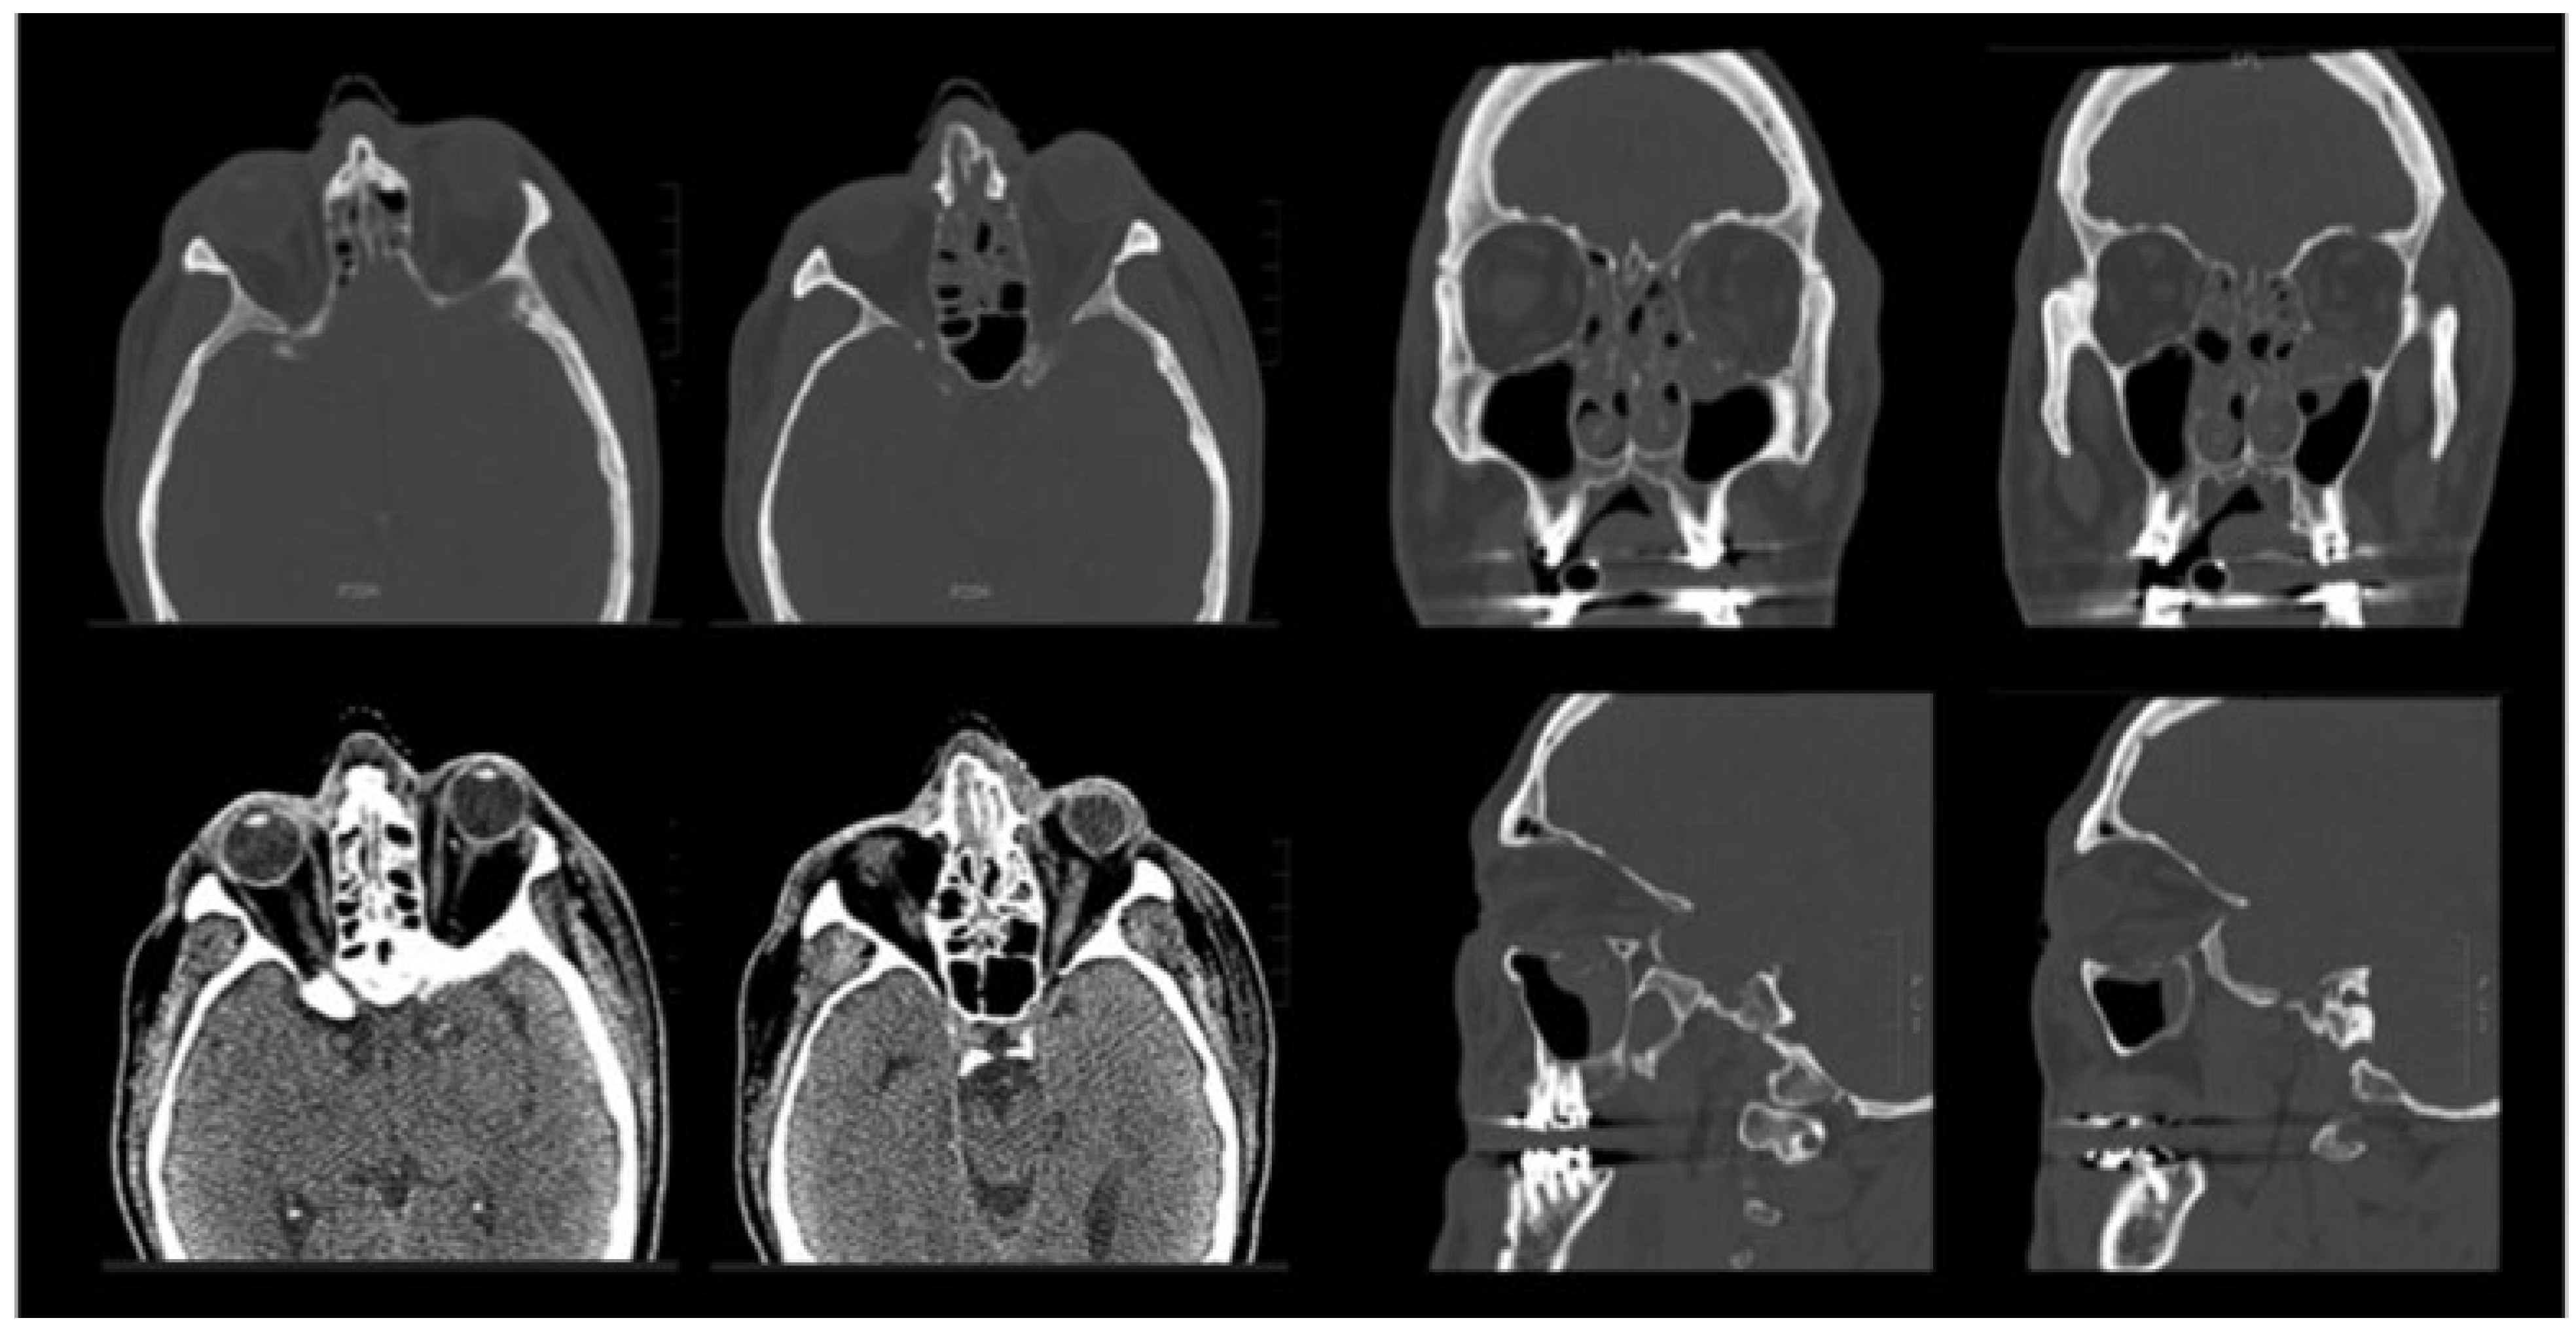

Maxillofacial computed tomography demonstrated a fracture of the left orbital floor, with herniation of fat into the maxillary antrum and left nasal bone fractures, as well as a deviated nasal septum (Figure 2). There was no evidence of retrobulbar hemorrhage, inferior rectus entrapment, or fracture into the orbital apex. Routine preoperative laboratory evaluations, including coagulation studies, were unremarkable.

Figure 2. Preoperative computed tomography. Axial (top row), coronal (middle row), and sagittal (bottom row) images show a sizeable orbital floor defect with herniation of soft tissue contents into the maxillary antrum, without evidence of extraocular muscle entrapment, globe injury, or retrobulbar hemorrhage.